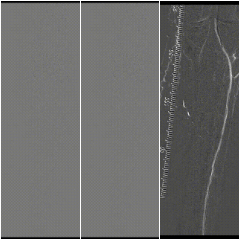

图:术中CT

3

手术结果

图:术后效果